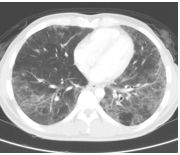

3. This 72-year-old diabetic man was taken to ER for productive cough for 10 days, and rapid progressive dyspnea for 2 days. He also had fever and chill for a week.